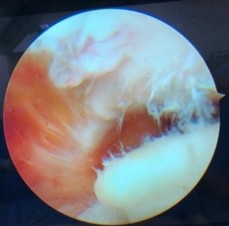

- Tình trạng viêm túi hoạt dịch trong khoang dưới MCV nếu có.

Hình 2.17. Tình trạng viêm túi hoạt dịch dưới MCV và xước điểm bám của dây chằng cùng quạ

* Nguồn: ảnh chụp trong mổ của BN Lê Cao S, mã số bệnh án 1911250706